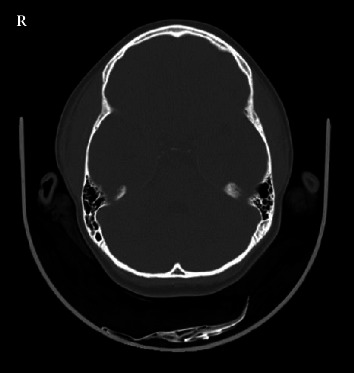

Primary infection by the Epstein-Barr virus (EBV) is common in children, can affect multiple organs and be associated with a wide variety of clinical manifestations. We present the case of a 7-year-old female patient assessed in the emergency department for bitemporal swelling with a one-day evolution, following self-limiting odynophagia and fever 1 week earlier. Physical examination revealed a soft, bitemporal swelling, more evident on the right, painful on palpation, with no other inflammatory signs. The soft tissue ultrasound showed no alterations, and the CT scan showed thickening of the right parietotemporal epicranial soft tissues, of an imprecise nature. At a 2-week follow-up consultation, swelling had completely resolved. The serological study revealed previous contact with cytomegalovirus and positive EBV IgG and IgM with negative EBNA IgG and EA IgG, indicative of acute EBV infection. Bitemporal oedema is a very atypical and rare presentation of primary EBV infection, with very few cases previously reported. The aim of this clinical case is to draw attention to the importance of considering EBV infection in the differential diagnosis of situations like the one described.